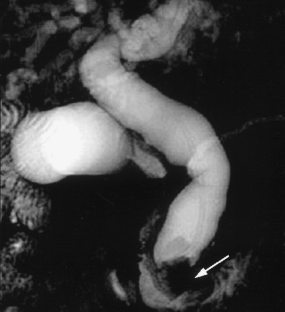

Usual and unusual causes of extrahepatic cholestasis: assessment with magnetic resonance cholangiography and fast MRI

Cholestasis may result from hepatocellular (intrahepatic) disease or biliary tract (extrahepatic) abnormalities. Etiologies causing extrahepatic cholestasis are extremely diverse and invasive procedures, such as endoscopic retrograde cholangiopancreatography (ERCP) and percutaneous transhepatic cholangiography (PTC), were previously required to establish the diagnosis. Due to refinements of magnetic resonance imaging (MRI) techniques, the patient with extrahepatic cholestasis currently can be evaluated noninvasively, and the information revealed frequently exceeds the findings obtained by ERCP and PTC. In this essay, we illustrate the classic MR cholangiographic (MRC) and MRI features of a variety of disorders causing extrahepatic cholestasis, including non-neoplastic disorders of the biliary tract (congenital abnormalities, infectious processes, iatrogenic disorders, and postsurgical complications) and neoplastic conditions (e.g., tumors of the pancreas, biliary tree, liver, ampulla, and regional lymph nodes). In most cases, familiarity with the key MRC features in addition to information obtained via cross-sectional MR images provide sufficient information for adequate lesion characterization.